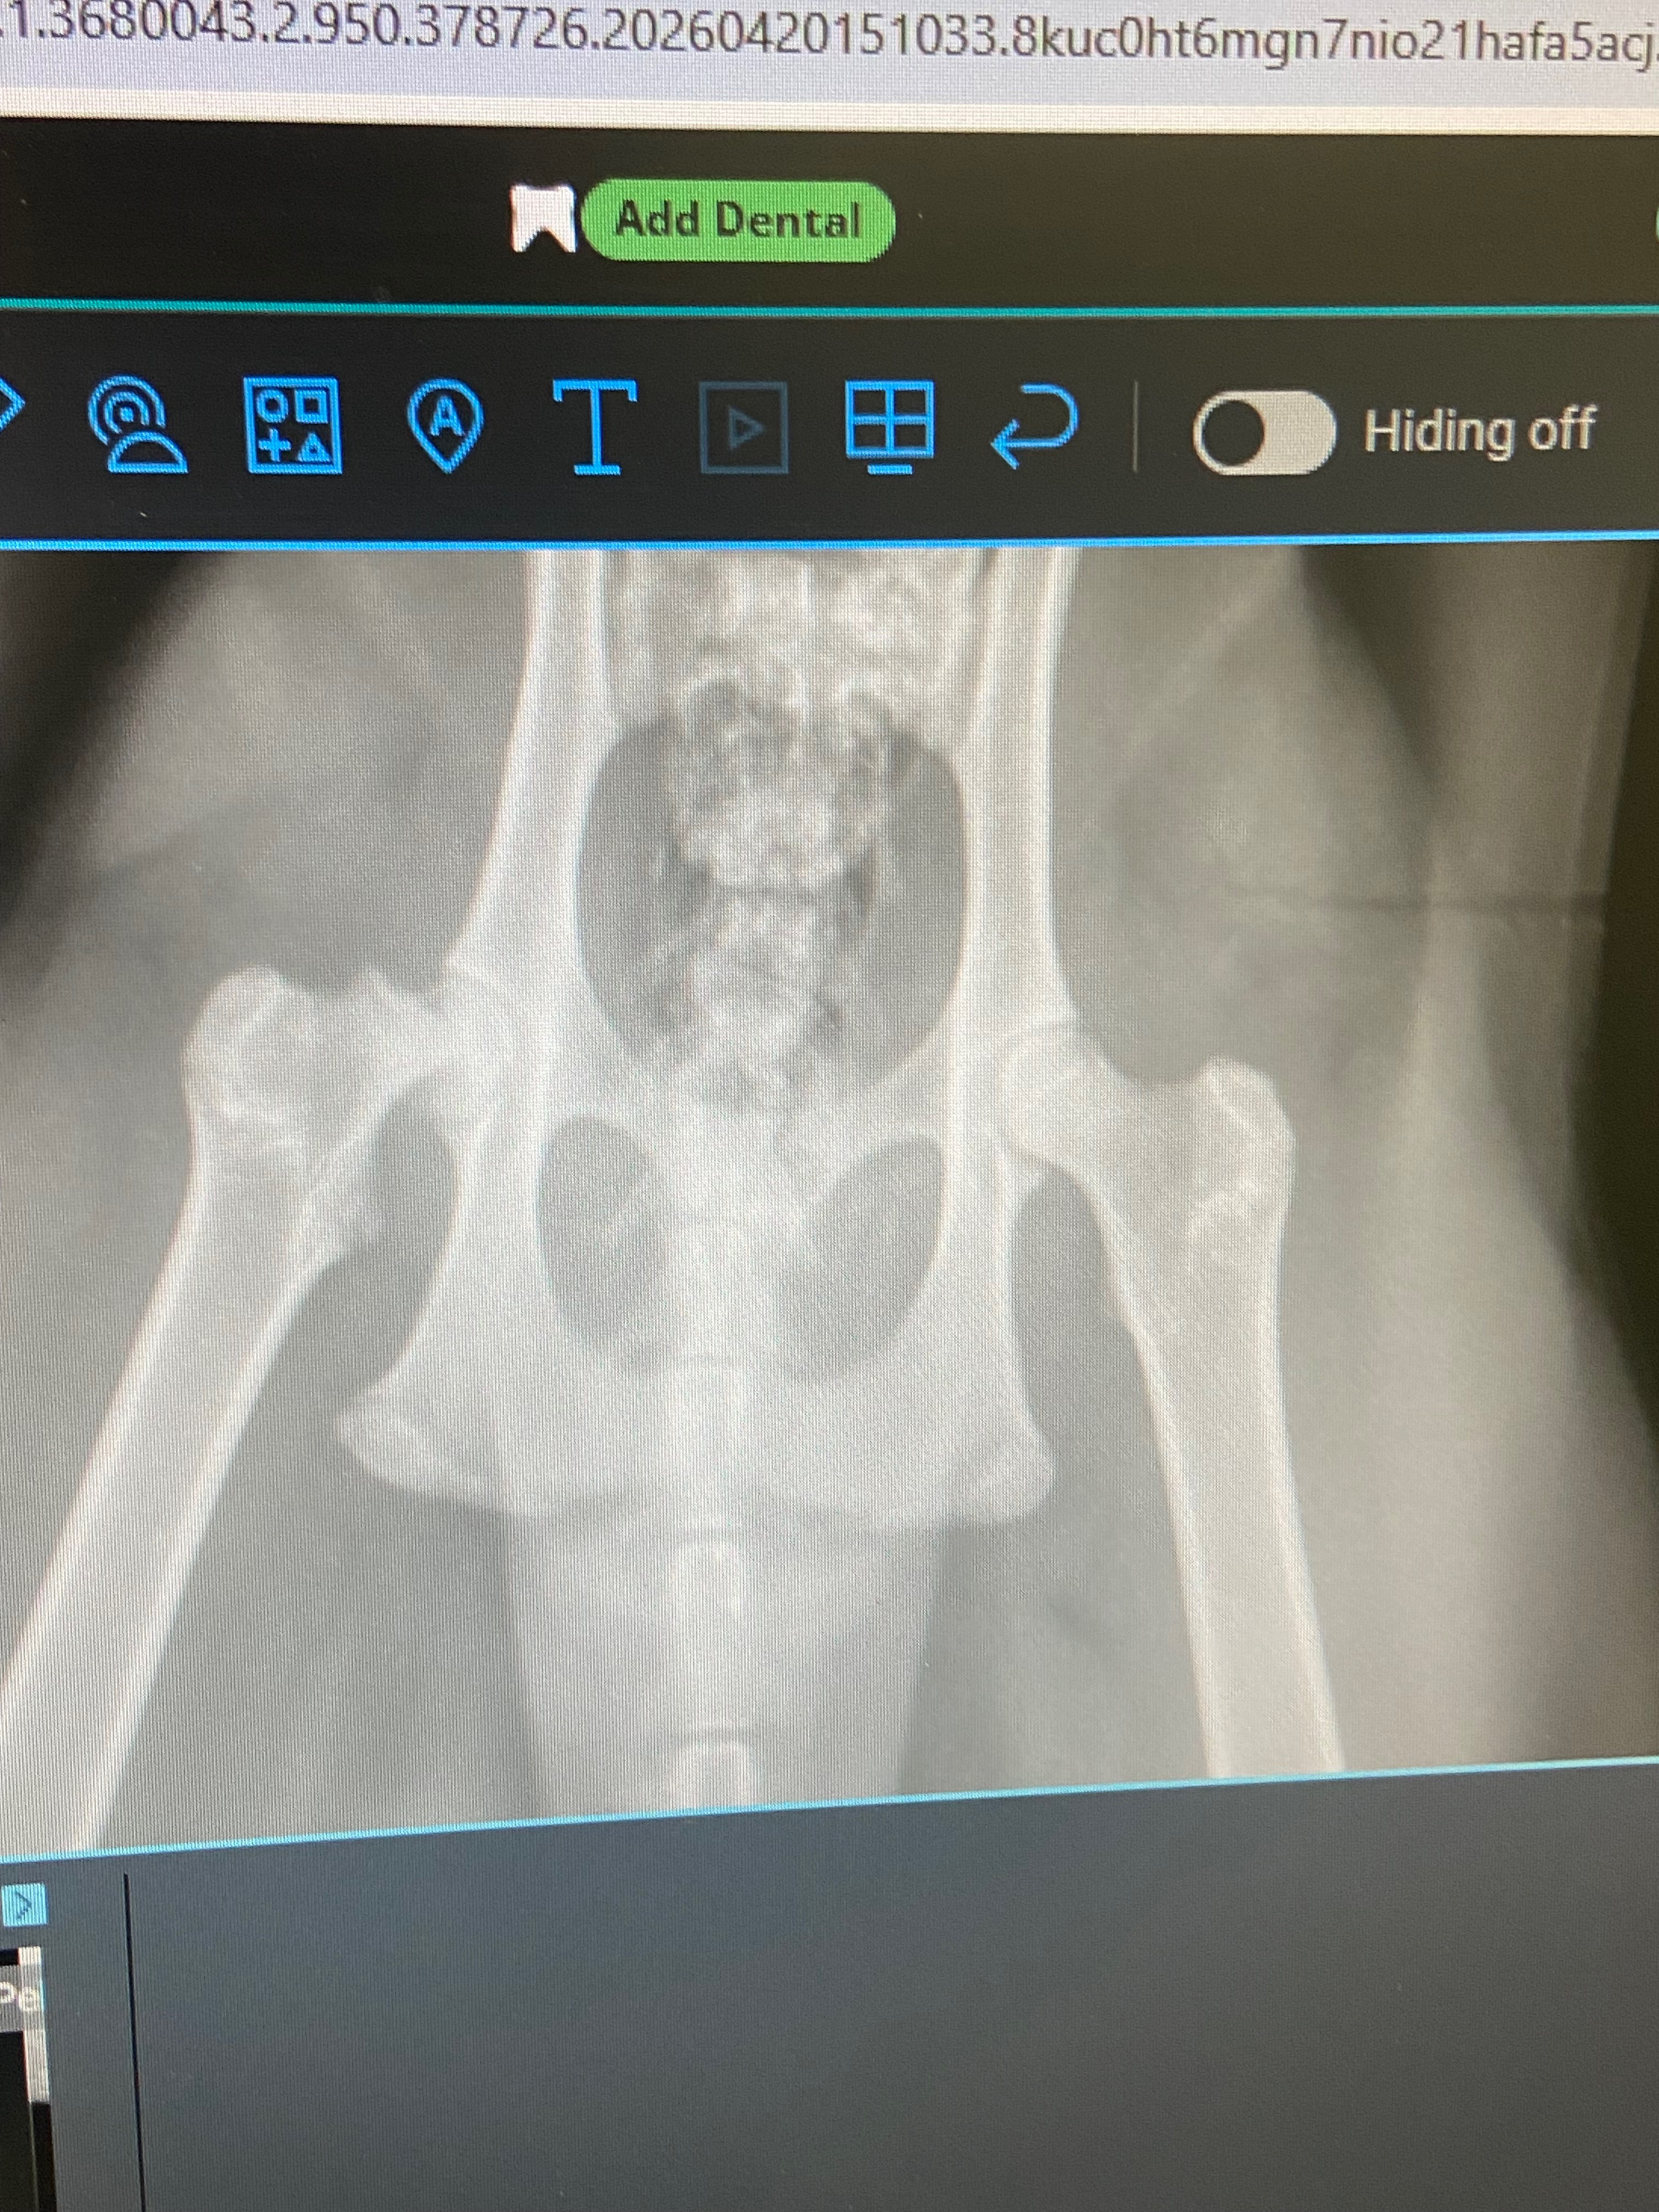

Ozzy, my sister’s beloved cat, has always been a gentle and shy companion who brings comfort to our family. This morning, we found Ozzy in pain and quickly learned that he had not only broken his arm but also his hip. The news was heartbreaking, and after urgent scans, it became clear that he needed emergency surgery to have a chance at a full recovery.